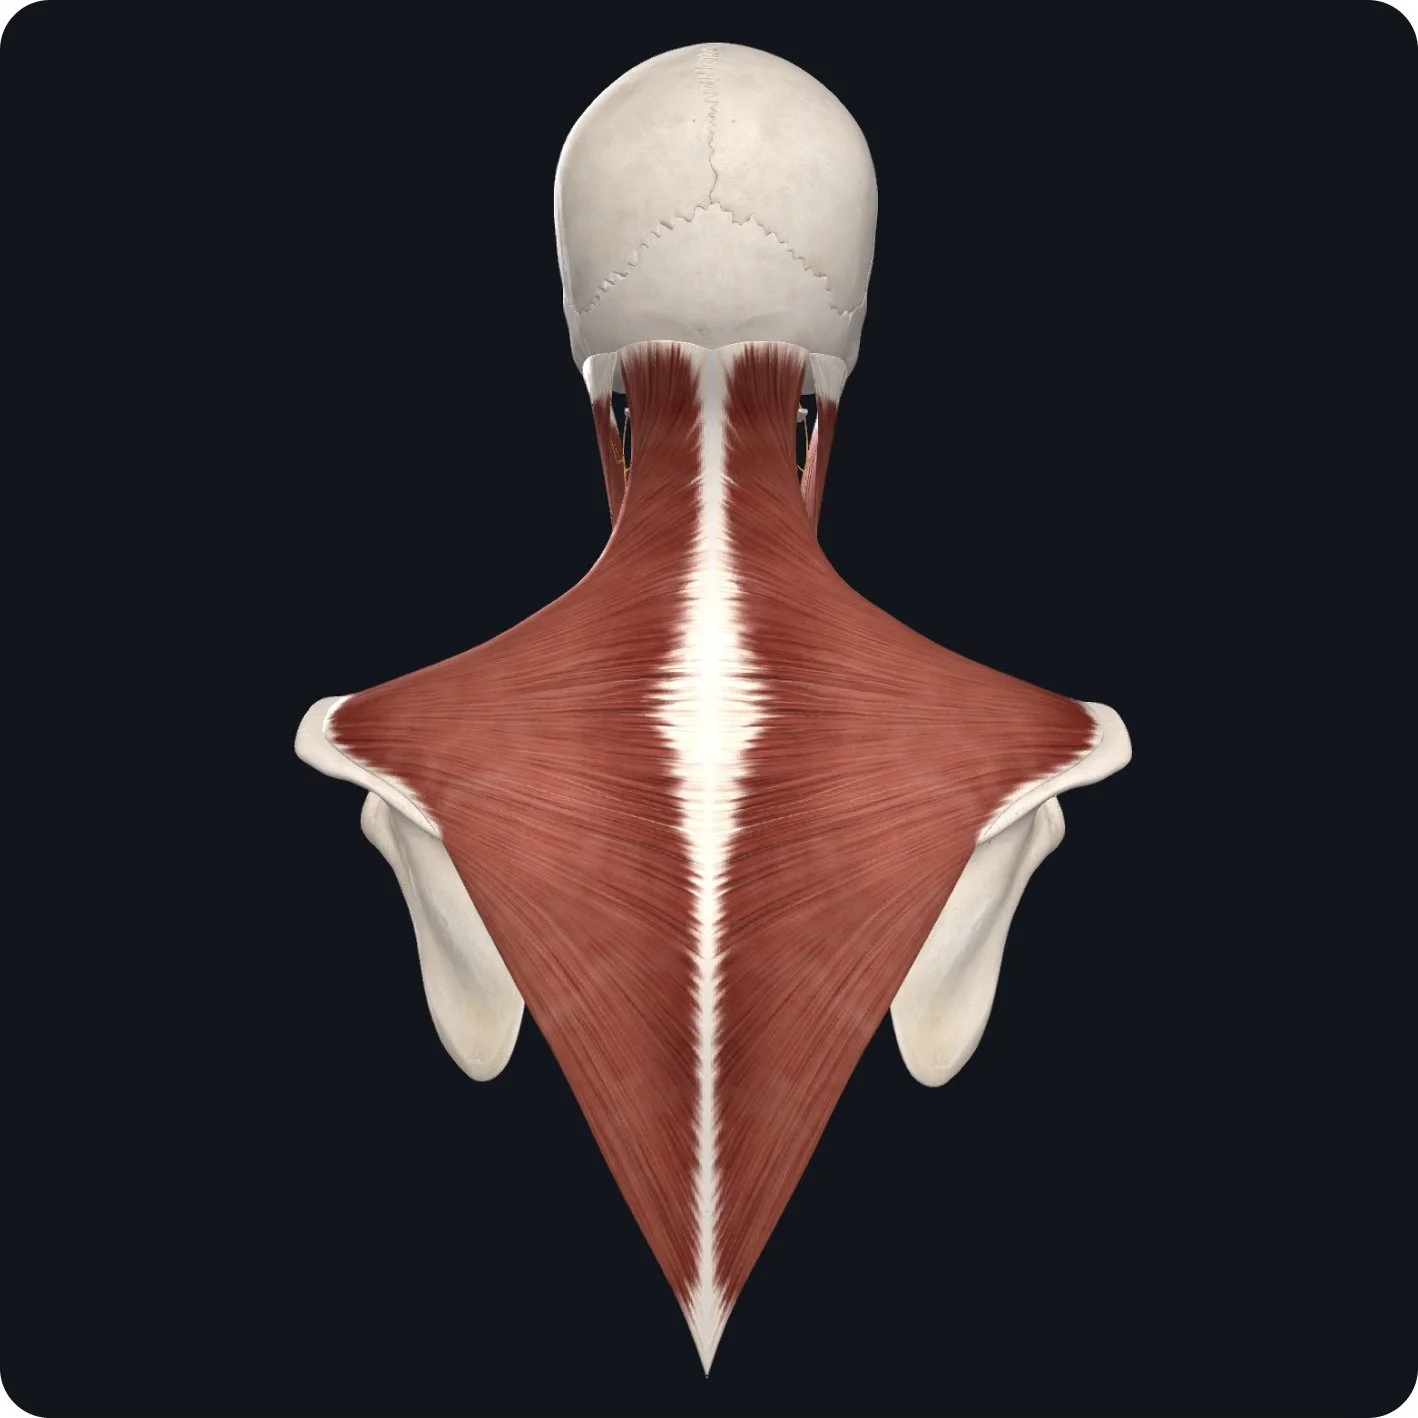

The accessory nerve also innervates a large muscle in our back, the trapezius muscle.

The trapezius muscle elevates the scapula, retracts the scapula, and depresses and rotates the scapula.